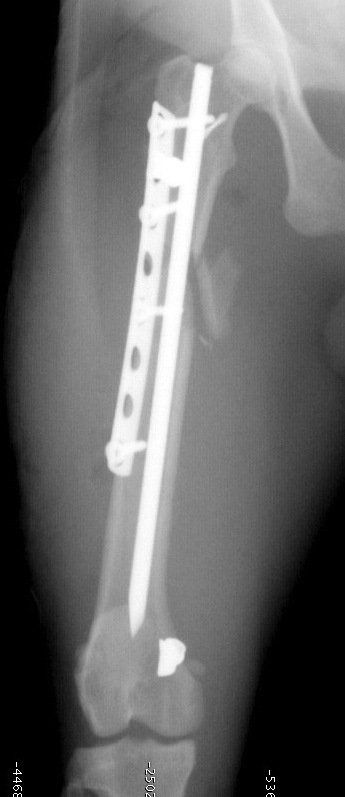

- Les chirurgies réparatrices lors de fractures des membres avec utilisation de broches, plaques et vis.